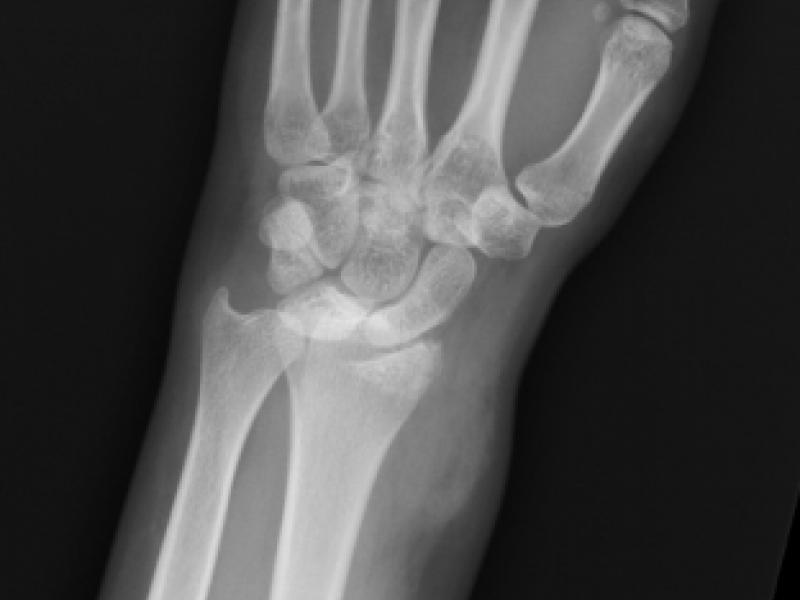

A 25 year old female presents after a motor vehicle